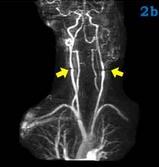

外科頸動脈體瘤癥狀

• 外科頸動脈體瘤